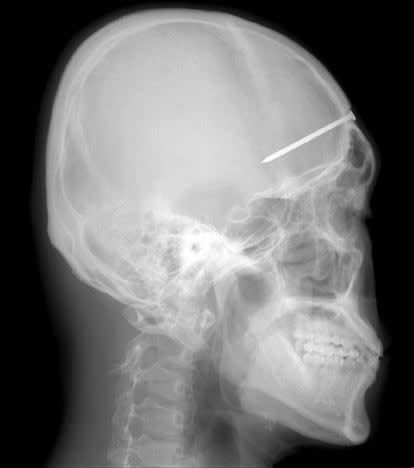

5-Centimeter Nail Lodged Skull for Four Years : Man Remain Unaware

South Korea: In a startling medical revelation, a South Korean man discovered a 5-centimeter nail lodged in his skull after complaining of a severe headache. The incident dates back to 2004, and doctors believe it may have occurred in an accident four years prior to the patient seeking medical attention.

The unidentified man visited a Seoul hospital, where an X-ray unveiled the unexpected foreign object in his skull. The man, unaware of the nail’s presence, had been experiencing severe headaches, leading him to seek medical help.